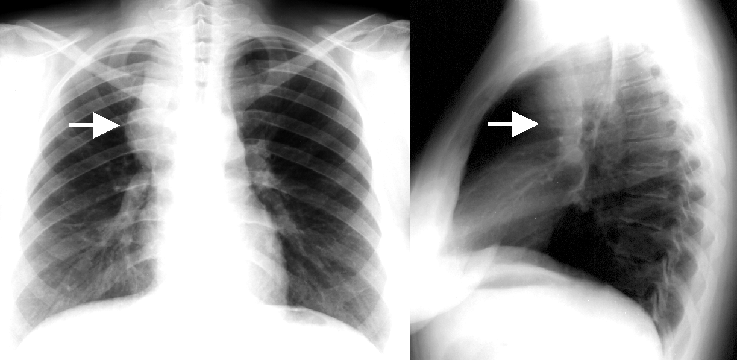

23. Pulmonary metastases, bidirectional (PA and right lateral) plain chest radiograph.

51 year old woman, endometrial carcinoma. Numerous ring shadows bilaterally in basal dominance (max. appr. 12 mm). Left pleural effusion of one finger wide.